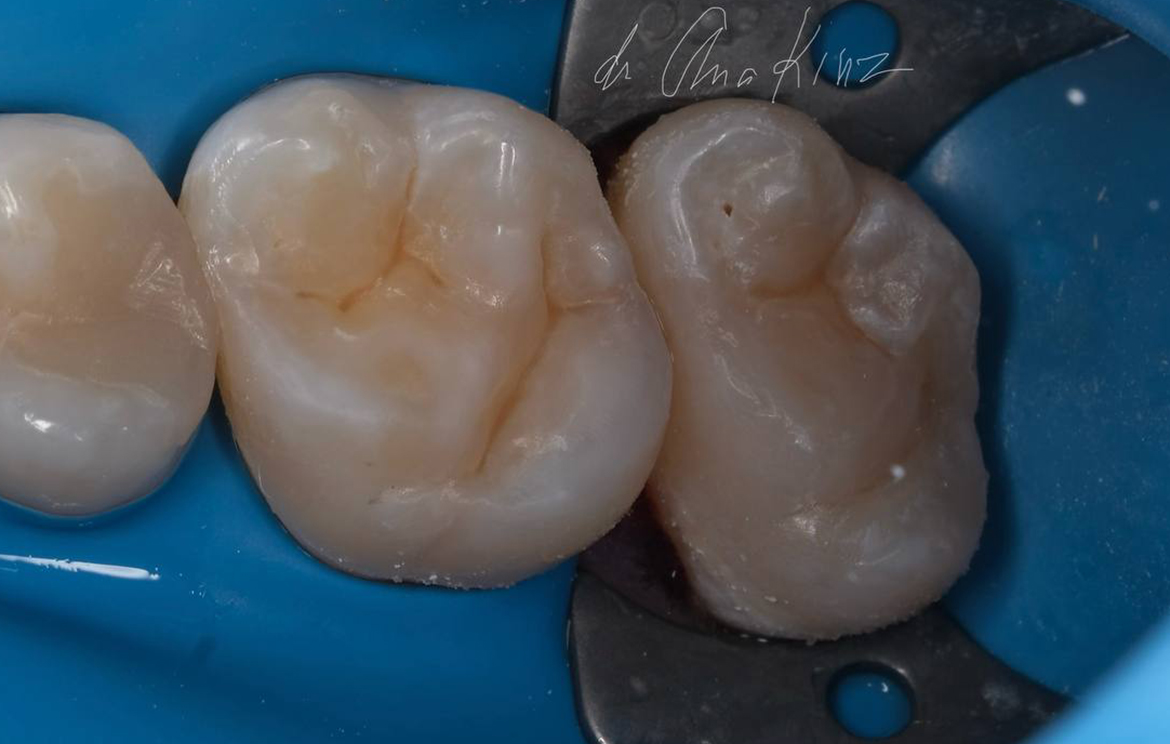

Наши работы